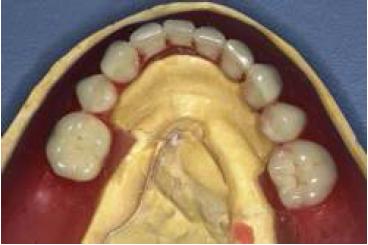

El inicio del tratamiento rehabilitador corresponde a los mismos pasos clínicos para la confección de una prótesis removible convencional, tanto superior como inferior, es decir: impresión primaria, confección de placa de altura con base acrílica y recorte de flanco lingual entre premolares similar a lo propuesto por Aalam et al. en 200510. Luego corresponde la prueba de placa de altura y determinación de plano protético inferior, determinación, registro y transferencia de relaciones intermaxilares, montaje y prueba de articulación dentaria (fig. 2). En el caso de la prótesis superior esta se terminó e instaló.

Enfilado dentario sobre modelo de trabajo con recorte de flanco lingual entre los premolares.